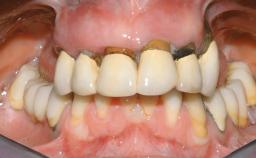

Immediate Loading of Eight Implants in the Maxilla and Six Implants in the Mandible and Final Restoration with Three-Unit and Four-Unit FDPs

Extensive scientific evidence has confirmed that immediately loaded implants with fixed full-arch provisional restorations can osseointegrate with success rates similar to conventionally or delayed loaded implants. A number of immediate-provisionalization techniques for edentulous jaws have been described. Some protocols differ when it comes to prefabricated provisional templates versus complete denture conversion; intrasurgical impressions versus direct relining; and cemented versus screw-retained provisional restorations. In this context, complete-denture conversion has been proposed for either intrasurgical impressions or direct relining. Another possibility is the utilization of a prefabricated provisional to be adapted either in the mouth (by direct relining) or in the laboratory (on a working model obtained from an intrasurgical impression).

Case Type Edentulous Maxilla

Jaw Maxilla and Mandible